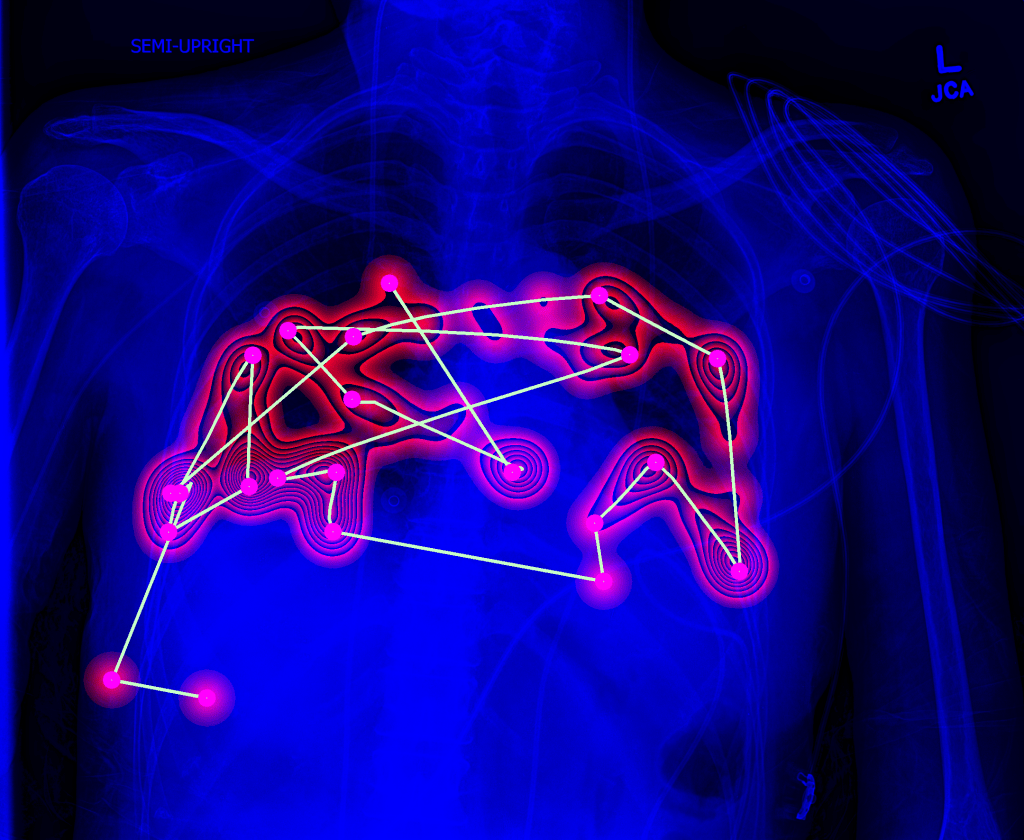

Lung image analysis

Chest X-rays is the most commonly acquired medical image worldwide. The advances of machine learning allow automated diagnosis of main lung pathologies, such as pneumonia and pneumothorax, with close-to-human performance. The automated diagnosis still however fails on patients with rare pathology manifestations, which precludes clinical integration of computerized solutions. The aim of this project is to develop solutions that will interact with physicians to improve lung disease diagnosis.